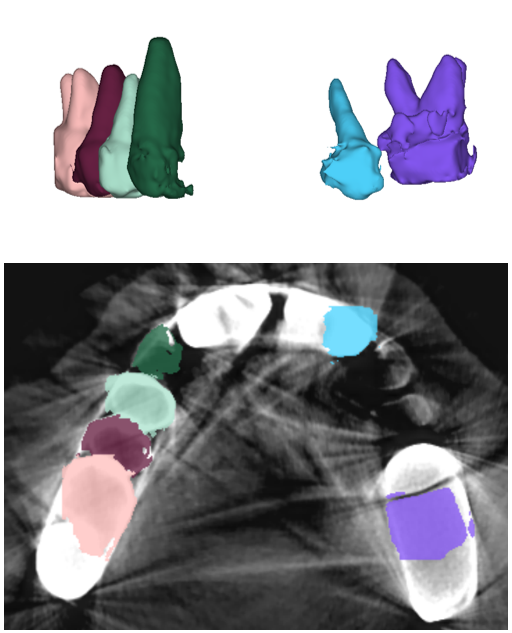

The manual seeded level-set methods [6, 7] demonstrate inferior performances while segmenting teeth with predominant metal artifacts (Table II). The energy-based (i.e., level-set function) algorithmic approach failed while defining an optimum stopping criterion (Fig. 12b). The AJI measures for level-set methods are omitted because the box detectors do not exist in the level-set-based methods. In particular, the low precision and sensitivity values indicate that level-set methods have over-segmented or under-segmented the teeth in many cases (Figs. 12b and 13a). The accuracies of the Mask-RCNN [17] and ToothNet [11] showed comparable performance to the level-set-based methods. The instance segmentation framework successfully detected and segmented the teeth automatically. However, it failed to detect all the teeth regions accurately, which resulted in a degradation of the segmentation performance. Moreover, the performance of the segmentation itself also showed low accuracy owing to the metal artifacts (Figs. 12c and 12d). Figure 13 illustrates the more severe conditions of metal artifacts. The performance of the detection and segmentation processes significantly degraded in ToothNet [11] (Fig. 13b) and Mask-RCNN [17] (Fig. 13c). Conversely, our proposed method outperformed the other state-of-the-art methods (Figs. 12e and 13d); further, the comparison between the PA- and non-PA-based results also demonstrated that the employment of a PA detector significantly improved the proposed architecture (Table II). The superior AJI value clearly shows that successful detection improved the overall performance.

Table III shows that our proposed TSNet is superior to other networks in a stand-alone segmentation performance (i.e., using the ground-truth boxes). Moreover, the overall performance of the networks that utilized PA-based ground-truth (PAGT) showed better accuracy than the ones that used the original image axes. The original 3D U-net [26] and others failed to segment the teeth with metal artifacts (Figs. 14 and 15). The DenseVNet [35] showed relatively higher precision than the 3D U-net [26] and VoxResNet [27] as DenseVNet employed a shape-prior based on trainable parameters [35]. The trained shape-prior based on well-bounded images suppressed the false positive responses. However, DenseVNet demonstrated inaccurate segmentation (i.e., sensitivity) due to the large shape variance of teeth.